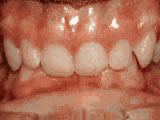

Phase-One

Patient's parents were concerned about both aesthetics and the health of the erupting permanent teeth when they brought him to the orthodontist at age eight. The lower front teeth were crowded and touching the palate, and the upper front teeth were extremely displaced from their normal positions. After 12 months of Phase-One treatment with an expander and partial braces, patient's appearance and dental function were vastly improved.